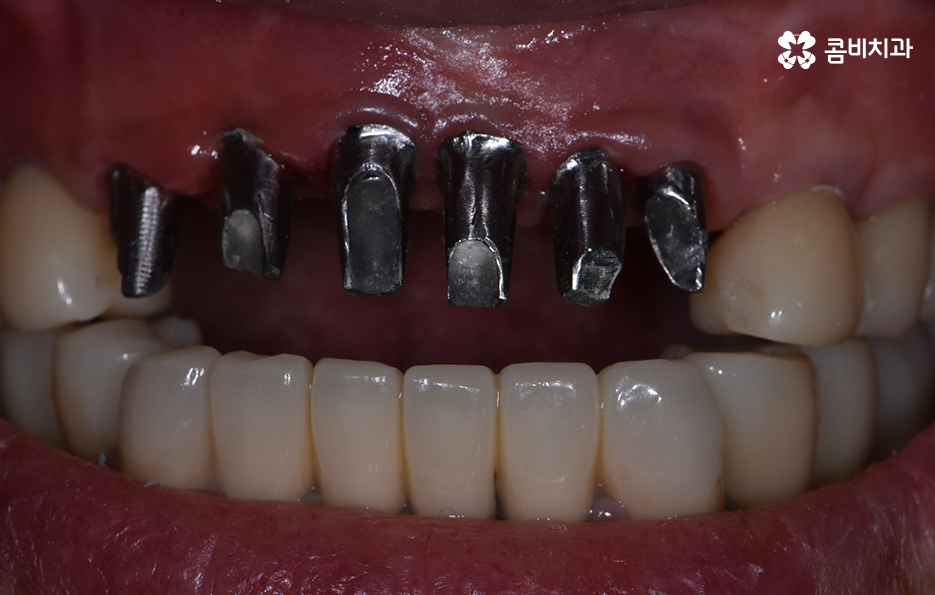

기존 치아의 색과 모양에 어울리는 보철물을 씌워서 마무리하는 과정

앞니를 잃게 되었을 때 주의해야 할 점

65세이상임플란트 기본적으로는 건강하고 안전하게

마무리가 되어야 하겠지만 앞니와 같이

평상시 대화를 할 때 주로 보이는 부위의 경우에는

심미성에 대해서 충분히 생각을 해야 합니다.

앞니는 사고로 인해서 잃게 되는 경우도 많기 때문에

젊은 분들도 잃게 되시는 경우가 종종 있는데요.

주변 치아와 비슷한 색으로 보철물을 선택하여

씌우기 때문에 시술이 끝나면 차이를 알아보기

어려울 정도로 심미적인 회복이 되는 경우가 대부분입니다.

모든 시술이 마무리 된 상태